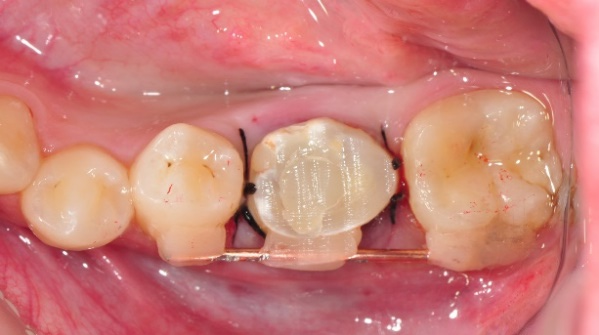

2.將智齒植入大臼齒位置,用鐵線固定

等待傷口恢復(約三個月)3.拆除固定鐵線、並將牙齒修型